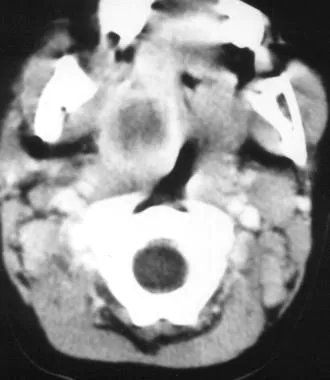

КТ шеи, показывающая левосторонний перитонзиллярный абсцесс.Признаки и симптомы инфекций глубокого пространства шеи

КТ с контрастированием являются золотым стандартом в оценке визуализации глубоких инфекций шеи.